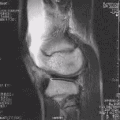

MRI

Both anterior cruciate ligament (ACL) and posterior cruciate ligaments (PCL) are hypointense on both T1 and T2 weighted images of MRI. However, some high signal striations are often seen at the distal part of the ACL, making ACL higher intensity than PCL on MRI scans.[20]

-

Knee MRI (PD TSE FS sagittal) -

Knee MRI (T1 TSE sagittal) -

Knee MRI (sagittal TSE FS)